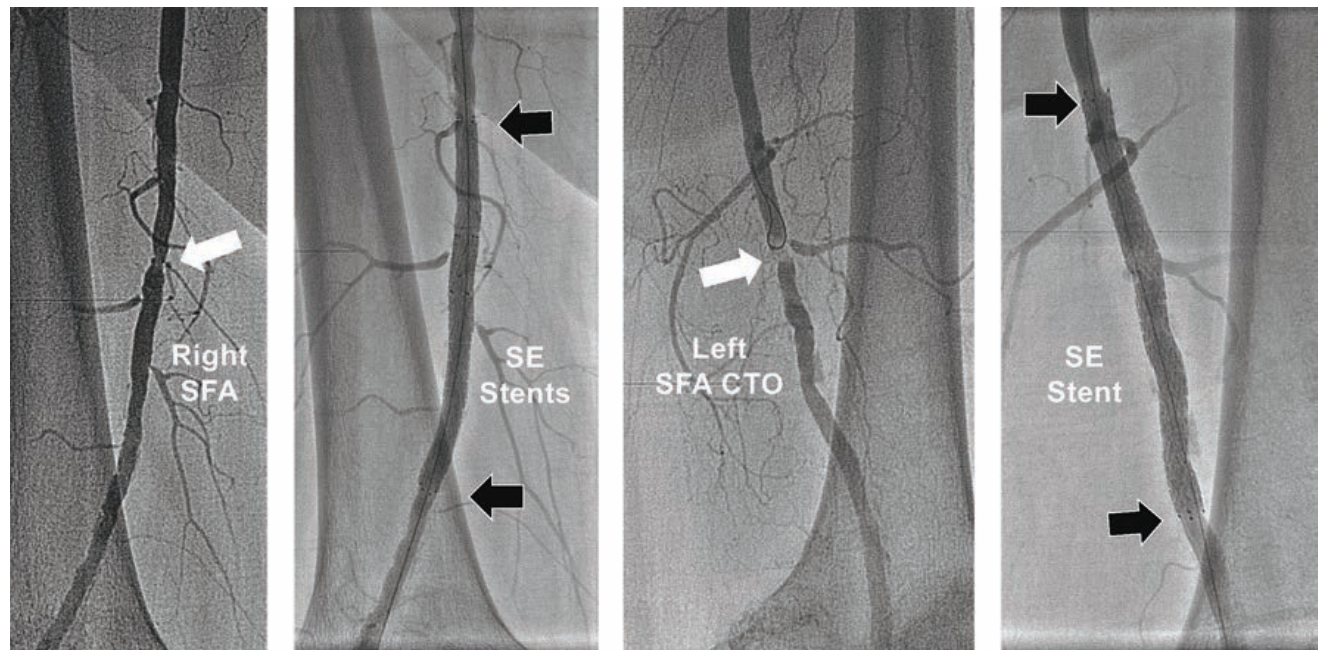

Case #1

A 68-year-old Native American female (5 feet 2 inches, 157 cm in height) with disabling left calf claudication and resting left ankle-brachial index (ABI) of 0.68 was referred for consideration of endovascular therapy. Diagnostic angiography using 5 Fr left TRA revealed severe left SFA disease with a lesion length of 25 cm, including 90% proximal SFA stenosis, with 3-vessel tibial runoff (Figure 1). A 300 cm .035-inch Wholey guidewire (Medtronic) was used to direct a 120 cm .035-inch 5 Fr Sublime guide sheath (Surmodics) into the left common femoral artery. Using this guide sheath, a 150 cm .035-inch 4.3 Fr TrailBlazer support catheter (Medtronic) was advanced over the Wholey guidewire across the SFA disease into the distal popliteal artery. A 320 cm .014-inch SpiderFX 6 mm capture wire (Medtronic) was deployed in the popliteal artery for embolic protection. Intervention was performed using two overlapping 6 mm x 150 mm 018 IN.PACT DCBs on 200-cm long catheters (Medtronic). After filter retrieval using the TrailBlazer catheter, filter inspection showed capture of embolic debris. Final angiography showed <30% residual SFA stenosis and no evidence for distal embolization. A TR Band (Terumo) achieved radial access hemostasis, with hospital discharge two hours later. At 9-month follow-up, the patient had no recurrent left leg claudication.

A 78-year-old short and obese Hispanic female (4 feet 10 inches, 147 centimeters in height, weight 200 pounds/90.7 kg) was referred with severe bilateral leg claudication, with critical limb ischemia due to a non-healing left foot wound. Using 5 Fr right TRA, abdominal aortography identified a right common iliac stenosis (Figure 3A). A 150 cm TrailBlazer catheter was advanced over a 300 cm Wholey guidewire into both common femoral arteries, and angiography revealed a short chronic total occlusion (CTO) of the left SFA, significant right SFA disease (Figure 3B), with 2-vessel tibial runoff into intact pedal arches bilaterally. The TrailBlazer catheter was further advanced over the Wholey guidewire to a level just above each SFA lesion, to confirm that the distance from right TRA to target lesions did not exceed 150 cm, the length of the device technology catheters being considered for therapy. In the right leg, following injection of 500 mcg of nitroglycerin through the TrailBlazer catheter, a significant 60 mmHg trans-stenotic pressure gradient was measured across the right iliac artery stenosis.

Using the Wholey guidewire, a 90 cm 5 Fr Flexor Shuttle sheath was first advanced into the left external iliac artery. The TrailBlazer catheter was positioned immediately above the left SFA CTO, and connected to a manifold using a Tuohy-Borst adapter (Cook Medical). This allowed injections of 2-4 cc of contrast for facilitating chronic total occlusion (CTO) crossing with a .014-inch 300 cm long Grand Slam (Abbott Vascular) coronary guidewire. Treatment was performed with an .018-inch Armada PTA balloon 6 mm x 60 mm on a 150 cm catheter (Abbott). A 5 Fr-compatible .035-inch EverFlex with Entrust delivery system self-expanding (SE) 7 mm x 80 mm stent on a 150 cm catheter (Medtronic) was deployed in the left SFA, then post-dilated with the Armada 6 mm x 60 mm balloon (Figure 3B). The Flexor Shuttle sheath was redirected using the Wholey guidewire into the right external iliac artery, with exchange for the .014-inch 300 cm guidewire. The right SFA was treated with overlapping EverFlex Entrust SE stents measuring 6 mm x 60 mm and 6 mm x 40 mm, with post-dilatation using an Armada 5 mm x 60 mm balloon (Figure 3B). Pre-dilation of the right common iliac artery stenosis was performed with a .014-inch Viatrac 14 Plus RX 7 mm x 15 mm PTA balloon (Abbott), followed by a .014-inch Herculink Elite RX 7 mm x 18 mm balloon-expandable (BE) stent (Abbott), both on 135 cm monorail catheters (Figure 3A). The patient was discharged 3 hours later following use of a TR Band. Her left foot wound healed within one month, her claudication resolved, and ABIs remained normal at two-year follow-up.